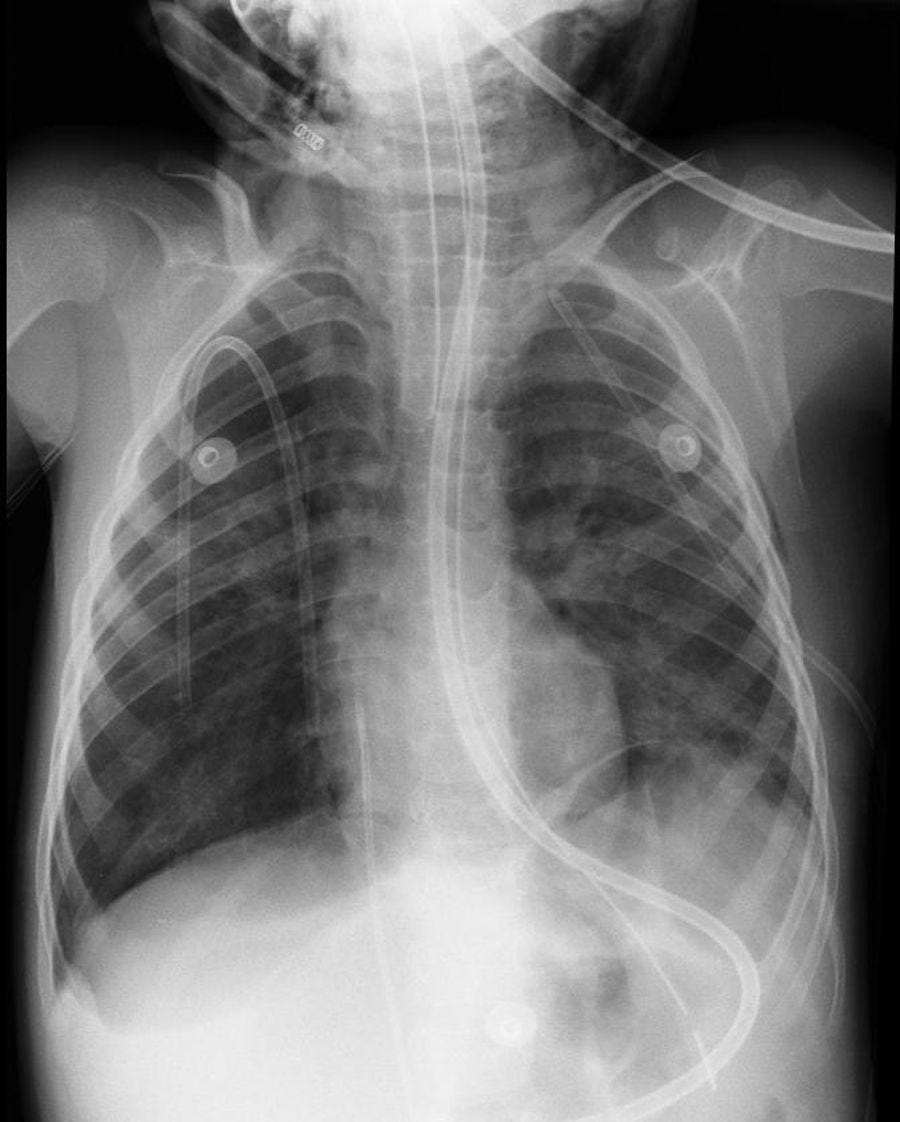

Bard PowerPort

The Bard PowerPort is an implanted catheter device used to deliver medications directly into the bloodstream, often for chemotherapy or long-term treatment. Lawsuits allege that the device can fracture or migrate, causing serious internal injuries, blood clots, infections, and the need for surgical removal. Manufactured by C. R. Bard, the product is the subject of a rapidly growing MDL. Plaintiffs claim the device was defectively designed and that safer alternatives were available. The litigation is currently in the coordinated discovery phase, with thousands of cases pending and expectations for future bellwether trials.